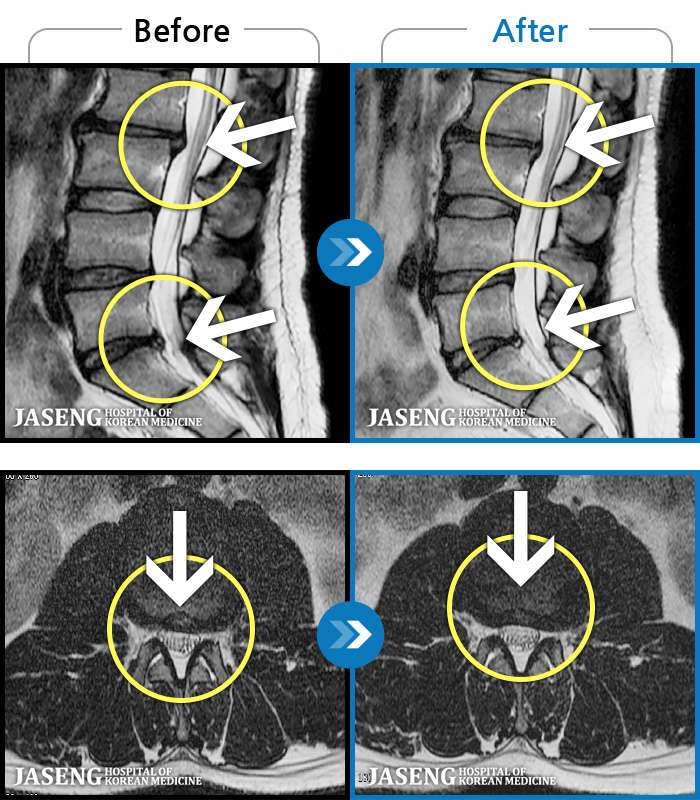

1,237 MRI ũ ʸ Ȯϼ.

MRI ġ

㸮 ϻ .